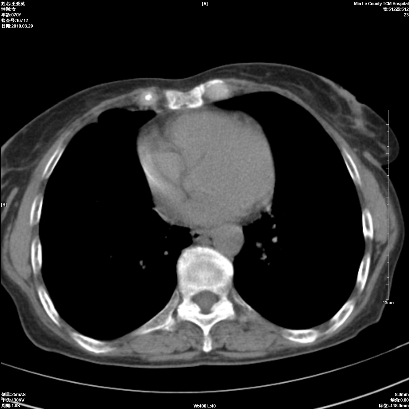

右肺上叶支气管开口阻塞,上叶呈不均匀致密影,右肺中下叶内见斑片状密度增高影,上叶见钙化点,纵隔内见钙化淋巴结,桶状胸,右下肺动脉增粗,残根征,意见:1.右肺中心性肺癌;2.右肺陈旧性结核;3.肺心病。

1)考虑右肺中央型肺癌伴右肺上叶肺不张,右肺门淋巴结转移;建议行支纤维镜检查。2)右肺中叶、下叶及左肺上叶舌段感染性病变。3)肝内多发低密度影,不排除转移瘤可能;建议行ct增强扫描检查。

ct所见:右肺上叶肺不张,呈软组织密度影向肺门区聚拢,其内可见含气段支气管及细支气管影,病灶内尚可见钙化结节。右肺上叶支气管狭窄,段支气管壁可见钙化。右肺下叶背段、右肺中叶见不规则小片絮状影及纤维条索影,形态较僵硬。右肺中叶胸膜旁可见多个小结节影。纵膈内见钙化淋巴结。

分析:右侧胸廓及右肺体积缩小,说明病变时间比较长了,应该是有数年的时间了,如果是短期内出现的肺不张,只会引起纵膈向患侧移位,而不会引起胸廓的塌陷。不张的肺组织内可见含气支气管影,说明右肺上叶支气管没有完全中断,只是狭窄。右肺中叶、下叶散在不规则病灶,部分呈纤维化改变。纵膈内的淋巴结大部分钙化。因此,本例给我的感觉良性病变的可能是大。

结论:考虑右肺上叶支气管内膜结核合并右肺上叶肺不张;右肺中叶、下叶陈旧性肺结核改变。